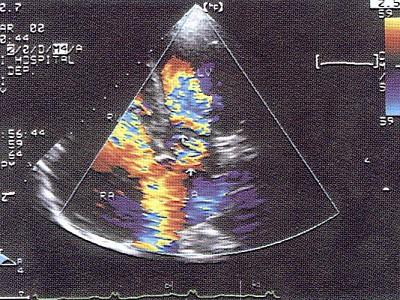

该病例最可能的诊断?(?)A.三房心B.瓣上环C.完全性肺静脉畸形引流D.冠状静脉窦扩张E.主动脉,肺动脉间隔缺损

问题 该病例最可能的诊断?(?)

选项 A.三房心 B.瓣上环 C.完全性肺静脉畸形引流 D.冠状静脉窦扩张 E.主动脉,肺动脉间隔缺损

答案 A